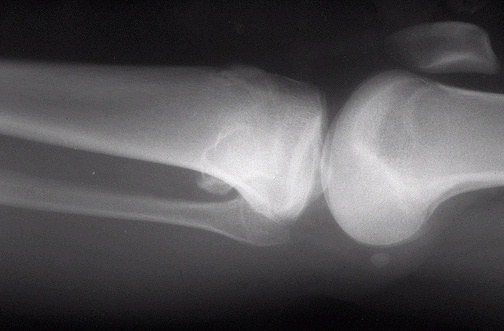

Image 5.1

The radiograph demonstrates a bony exostosis extending from the lateral portion of the tibia.